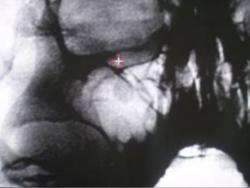

Протокол. На обзорной цифровой флюорограмме придаточных полостей носа (1) справа в гайморовой полости определяется каплевидной формы образование малой интенсивности, с четкими, ровными контурами, однородной структуры. Данное образование шейкой (тонкой ножкой) связано с верхней стенкой гайморовой полости. При обработке изображения в режиме «эквилизация» и с увеличением в 1,5 раза (2) – в условиях позитива и в 2,0 раза в условиях негатива (3) тень полипоподобного образования видна более отчетливо и структурно, намечается неоднородность тени.

1. Обзорная цифровая флюорограмма придаточных полостей носа

2. Режим «эквилизация» и с увеличением в 1,5 раза в условиях позитива

3. Режим «эквилизация» и с увеличением в 1,5 раза в условиях негатива